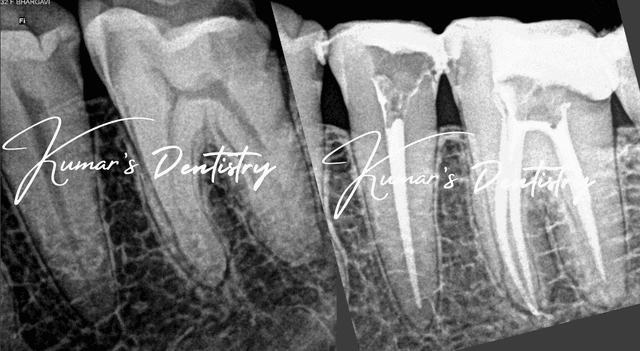

Advanced root canal treatment with 25x magnification for precision and success

25x magnification for precision and better outcomes